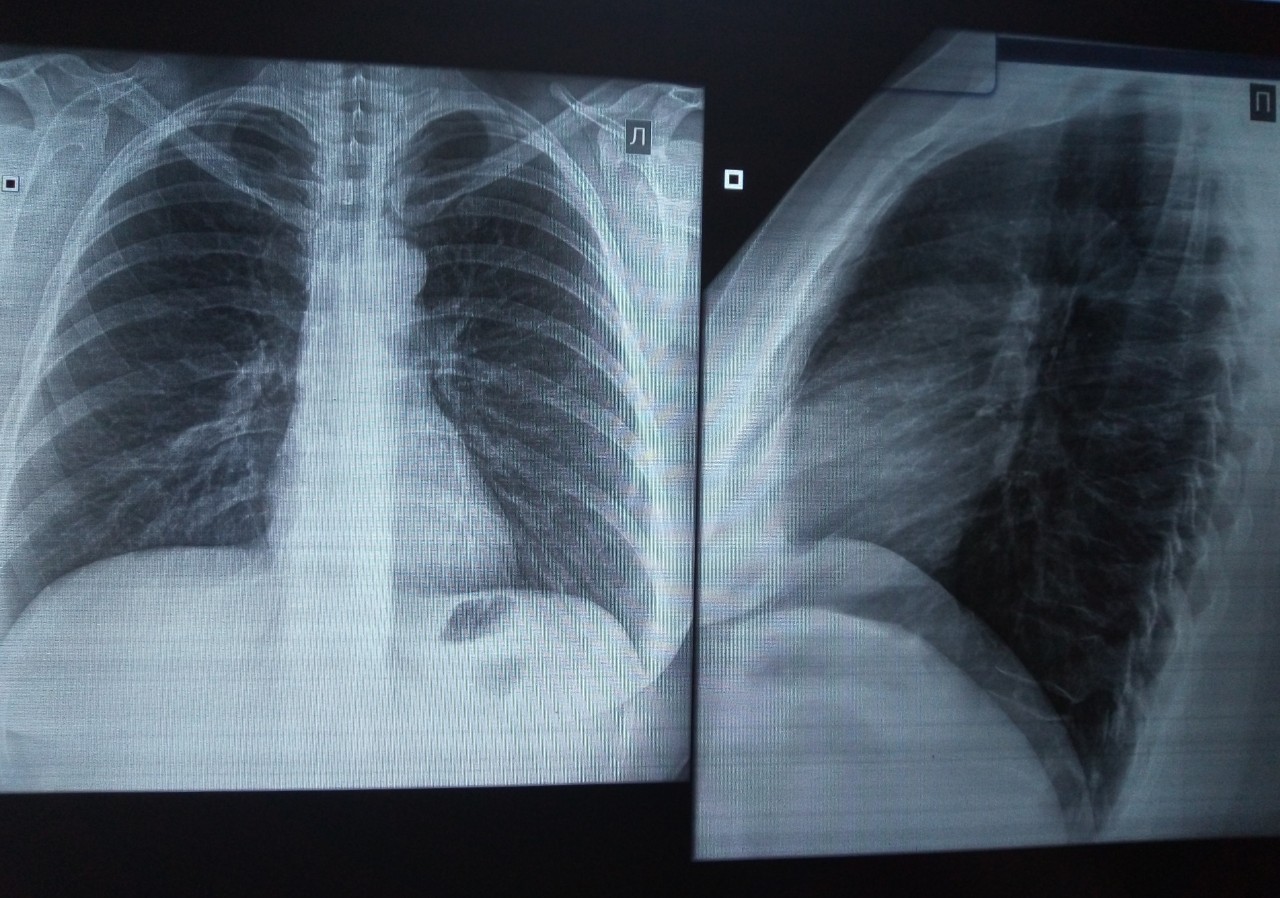

Снимок грудной клетки здорового ребенка: примеры и диагностика